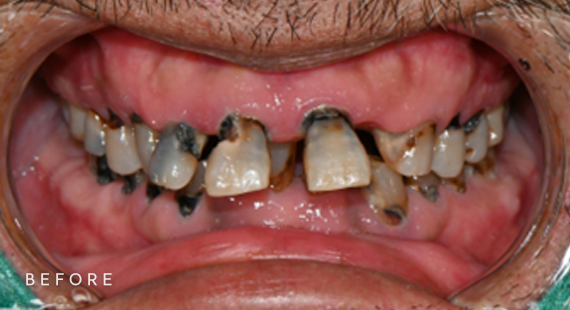

충치치료